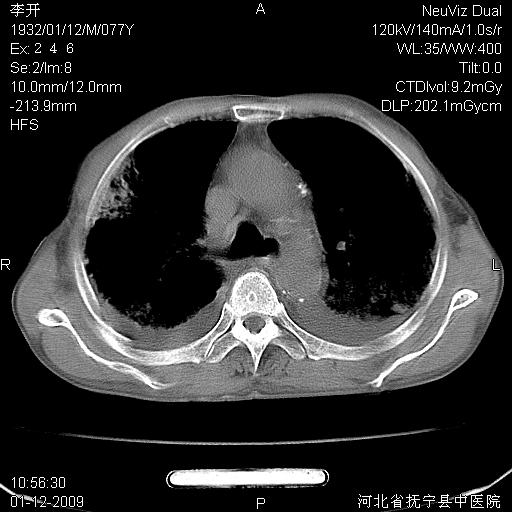

以下是引用黑白光影在2009-1-19 16:49:00的发言:[br]心衰肺水肿;心包、胸腔积液;冠脉钙化;肺部感染。